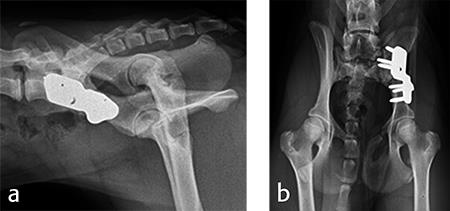

Angles of subluxation (10°) and reduction (30°) of the right hip were measured under anesthesia and the patient was placed in dorsal recumbency. A 7 mm portion of the right pubic body was excised. The patient was repositioned into lateral recumbency. A right ilial osteotomy was made immediately caudal to the sacrum. A 25° DPO/TPO plate was attached to the caudal ilial bone segment using locking 3.5 mm screws in the three stacked combi holes. The caudal acetabular segment was rotated laterally until the cranial aspect of the plate was in contact with the lateral aspect of the cranial ilial segment. The osteotomy site was compressed, and the plate was secured to the cranial ilial bone segment using a 3.5 mm cortical screw in the LCP combi hole in the cranial side of the plate. Three additional 3.5 mm locking screws were placed in the remaining stacked combi holes in the cranial segment of the plate.

Postoperative radiographs revealed reduction in subluxation with capture of the femoral head in the right coxofemoral joint (Fig 4). Palpation of the hip revealed good stability of the right hip. Activity was restricted to leash walk only for 6 weeks postoperatively. Radiographic examination 7 weeks following surgery revealed healing of the ilial osteotomy, stable implants, and excellent coxofemoral conformation and stability (Fig 5).

For each surgical procedure, the patient was placed in dorsal recumbency to enable the pubic ostectomy. The patient was repositioned in lateral recumbency to perform the DPO. A left ilial osteotomy was performed caudal to the sacrum. A 25° DPO/TPO plate was attached to the caudal ilial segment using locking 3.5 mm screws in the three stacked combi holes. The caudal acetabular segment was rotated laterally until the cranial aspect of the plate was in contact with the lateral aspect of the cranial ilial segment. The osteotomy site was compressed and the plate was secured to the cranial ilial bone segment using a 3.5 mm cortical screw in the LCP combi hole in the cranial side of the plate. Three additional 3.5 mm locking screws were placed in the remaining stacked combi holes in the cranial segment of the plate (Fig 9).